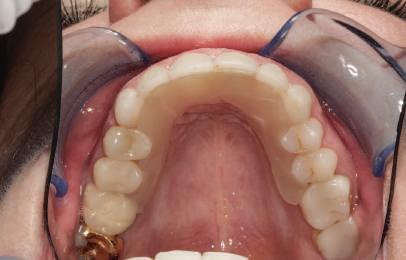

Conform informațiilor oferite de CBCT, pe pozițiile molarilor 36 și 37 au fost inserate două implanturi Ankylos (Dentsply Implants) C/X A 11 (diametru 3.5 mm, lungime 11 mm).

Datorită stabilității primare la inserare de aproximativ 35 Ncm pentru ambele implanturi, am optat pentru înșurubarea bonturilor intermediare conice Balance Base Narrow Straight GH 3.0 și vindecare transgingivală (fig. 2, 3). Inserarea acestor stâlpi s-a realizat la un cuplu de forțe de 25Ncm, cu ajutorul unei chei dinamometrice, aplicându-se ulterior cape de protecție (fig. 4). Vindecarea transgingivală postoperatorie a decurs fără complicații.

Figurile 1. Status clinic şi radiologic iniţial; 2. Bontul Balance Base Narrow Straight GH 3.0; 3. Bonturile Balance Base Narrow aplicate imediat post-inserare la 25 Ncm; 4. Aplicarea capelor de protecţie şi sutura; 5. Stâlpii de amprentă înşurubaţi la nivelul bonturilor Balance Base Narrow;